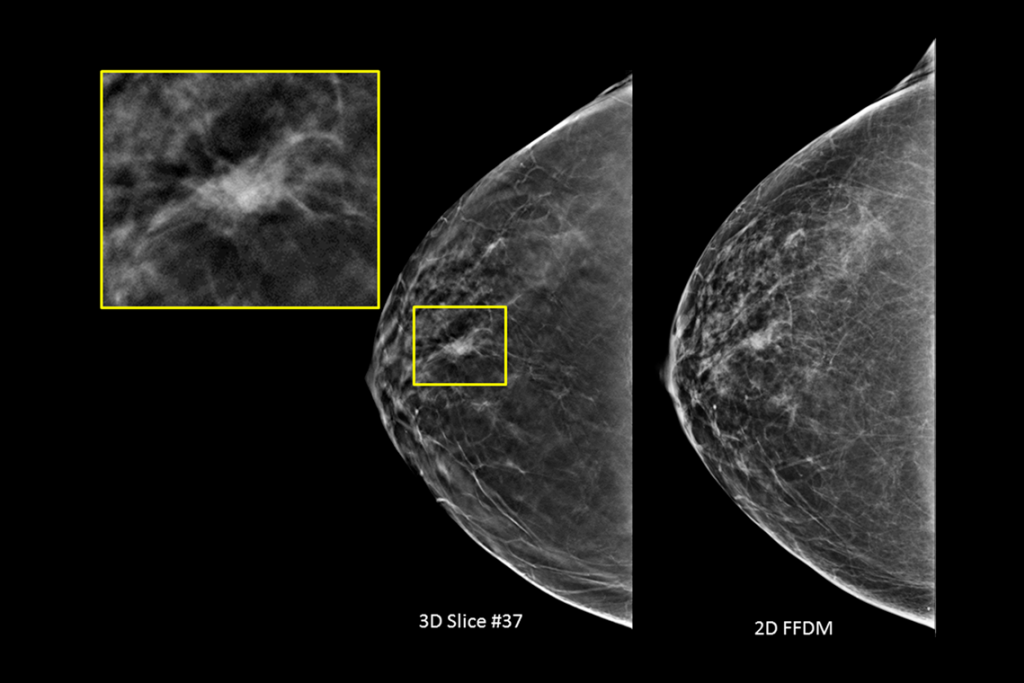

Immagini cliniche di una mammografia

Immagini cliniche di una mammografia con lesione sospetta

Immagini cliniche di una mammografia con tessuto mammario denso